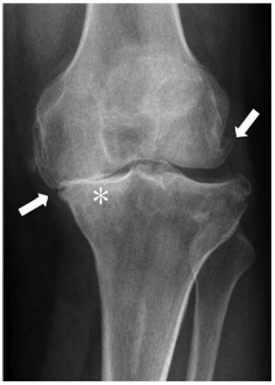

Outra classificação muito difundida dessa doença é a descrita por Ahlbäck. Segundo esse autor, classifica-se a radiografia representada na figura da questão 25 como grau:

Enunciado 4721074-1

Enunciado 4721074-2

Considere que a paciente do caso clínico relatado realizou o exame representado na figura. De acordo com a classificação de Kellgren e Lawrence, trata-se do grau

A classificação radiográfica Kellgren e Lawrence se baseia em três parâmetros que são